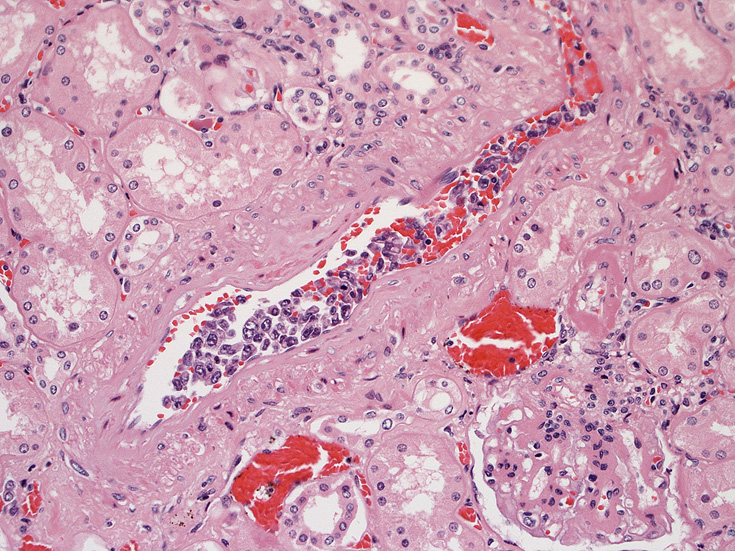

脳;くも膜下腔の小動脈内, 脳白質の細血管内に腫瘍細胞が充満している。

肺A;肺胞壁が厚くなり毛細血管内に腫瘍細胞が多数出現している(A).

肺B;小気管支動脈, 肺動脈内を腫瘍細胞が閉塞する. 動脈内膜に浸潤性増殖している(B)。

腎臓;糸球体係蹄内に腫瘍細胞が増殖するほか細腎動脈にもみとめられる。